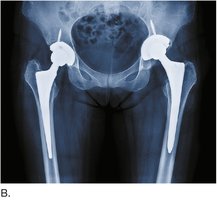

Hip Replacement

Total hip replacement involves removing the damaged femoral head and acetabulum and replacing them with prosthetic components.